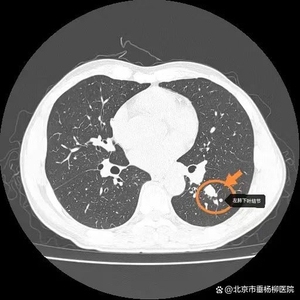

患者,中年男性,主因“发现左肺下叶结节伴肺门淋巴肿大1周”来诊,由门诊以“肺部占位性质待查”收入清华大学附属垂杨柳医院胸外科。入院后完善各项检查后,行经支气管超声引导纵隔淋巴结针吸活检术(EBUS-TBNA),冰冻病理考虑恶性肿瘤,具体结果待石蜡。患者术后第一天出现头晕、恶心呕吐,症状持续不缓解。给予对症止吐治疗,症状改善不明显。追问患者既往1月前曾有类似症状,可自行缓解。遂请神经内科、骨科及耳鼻喉科会诊,除外颅内病变、颈椎病及耳石症等相关疾病。患者血化验检查显示血钠118mmol/L,给予静脉及口服补钠后症状缓解。患者石蜡病理回报考虑纵隔转移性小细胞肺癌。结合病史考虑左肺下叶小细胞肺癌伴纵隔淋巴结转移,低钠血症为抗利尿激素分泌失调综合征。

胸部CT

左肺下叶结节